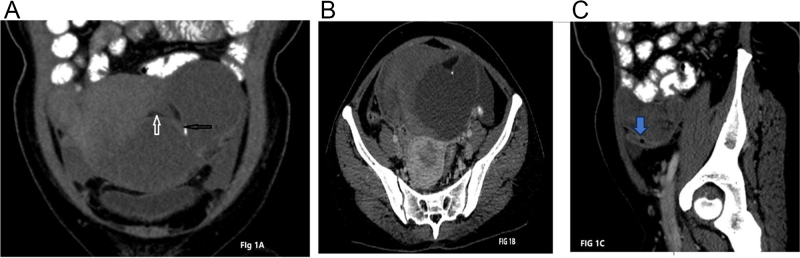

Case presentation: A 39-year-old woman presented with right lower abdominal pain, fever, and vomiting. Initially diagnosed with an appendicular lump, she was managed conservatively and discharged after symptomatic improvement. Upon recurrence of symptoms, imaging revealed an ovarian dermoid cyst with torsion. Exploratory laparotomy identified a gangrenous ovary with a twisted cyst and adherent appendix. Histopathology confirmed acute appendicitis and a benign dermoid cyst.

Discussion: Adnexal torsion occurs when the ovary and fallopian tube twist around their ligaments, often caused by ovarian cysts like dermoid cysts. These cysts are common in young women and can lead to acute abdominal pain, requiring urgent surgery to prevent ovarian damage. Diagnosis is challenging, as symptoms mimic other conditions like appendicitis. Imaging such as ultrasonography or computed tomography is used, and treatment involves surgical untwisting or removal of affected tissues. Torsion sometimes affects nearby organs, like an appendix.